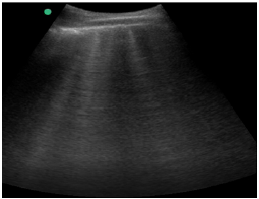

Um paciente de 50 anos de idade encontra-se, internado na UTI por conta de choque séptico de foco pulmonar, em ventilação mecânica na modalidade pressão e no modo assisto-controlado. Pela manhã foi submetido a acesso venoso central em veia axilar guiado por ultrassonografia. Ao exame físico, notou-se que o paciente está com hipotensão e taquicardia. A primeira hipótese diagnóstica é pneumotórax e é realizada radiografia com imagem apresentada.

Qual imagem abaixo corresponde ao achado ultrassonográfico para o paciente em questão?

De acordo com a imagem, a